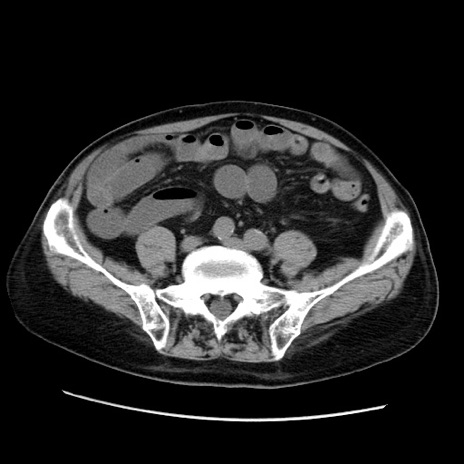

症例21(横断像)

冠状断像

【症例】70歳代男性

【主訴】腹痛

【現病歴】肝硬変・肝細胞癌にてかかりつけの方。約9時間前に食後より腹痛出現。症状が徐々に増悪し、嘔吐出現したため来院。

【既往歴】肝硬変、肝細胞癌(RFA、TACE後)

【身体所見】意識清明、表情苦悶様、BT 36℃、BP 129/78mmHg、P 88bpm、SpO2 97%(RA)、右上腹部から心窩部にかけて圧痛あり、反跳痛なし、筋性防御あり。

【データ】WBC 5800、CRP 0.16